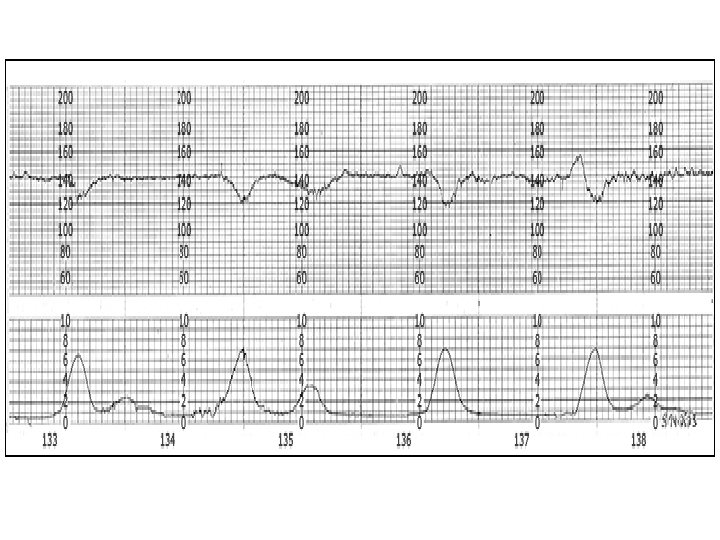

Early Deceleration Gradual decrease in FHR with onset of deceleration to nadir >30 seconds. The nadir occurs with the peak of a contraction.

Late Deceleration Gradual decrease in FHR with onset of deceleration to nadir >30 seconds. The nadir of the deceleration occurs after the peak of the contraction

Late Deceleration • Reflex • Myocardial depression

Recurrent Decelerations occur with > 50% of uterine contractions in any 20 minute segment. – Recurrent variable decelerations (at least 3 in 20 minutes) may be observed. However, close follow up is recommended because cord accidents with subsequent fetal death may occur even in the presence of normal amounts of amniotic fluid. – Recurrent late decelerations should lead to consideration of cesarean delivery unless the abnormal results are believed to be the result of a reversible maternal condition such as diabetic ketoacidosis or pneumonia with hypoxemia.